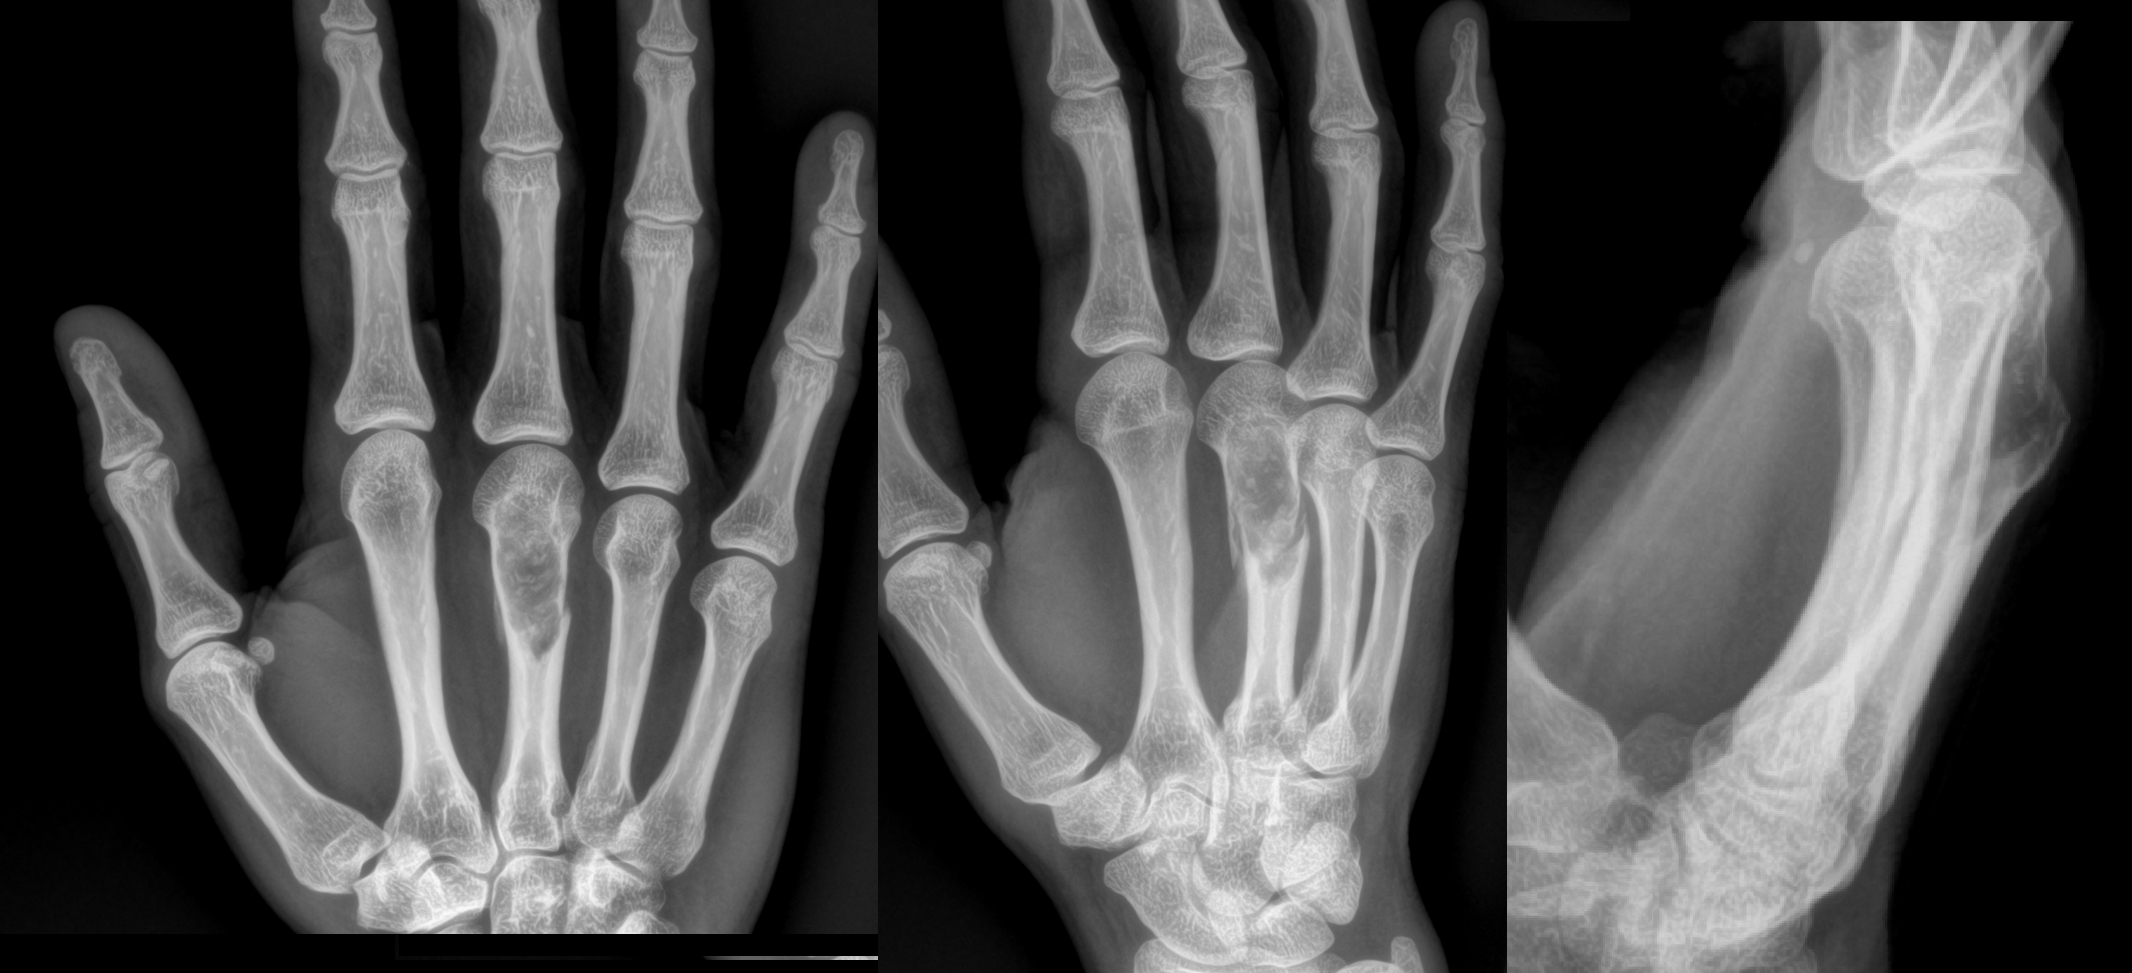

An 80 year old female presents to your office with a left ring finger deformity after a fall one week ago. She initially went to urgent care and xrays were unremarkable for a fracture (Figures 1 and 2). A photo of her left ring finger is shown in figure 3. On physical exam the left ring finger is in hyperextension at the PIP joint and flexion at the DIP joint. She able to flex her PIP joint with full motion. What is the best treatment option?